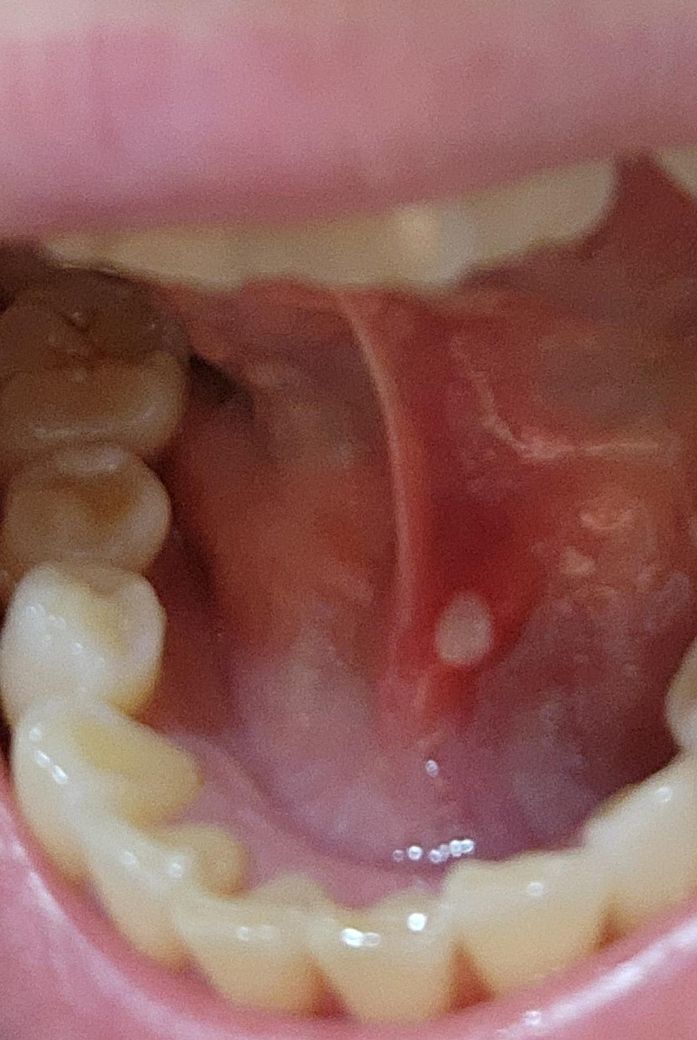

3일전부터 입안에 뭐가 난게 느껴져서 신경쓰였는데요. 아프기도 하고 ㅠ 사진 첨부했습니다. 내과를 가서 약을 지어먹어도되나요?

• 1번 째 사진

치과나 이비인후과 진료를 받는 것이 더 좋을 것으로 보입니다. 수분 섭취 부족, 수면 부족, 카페인 과다가 있으면 구내염이 잘 생길 수 있습니다.